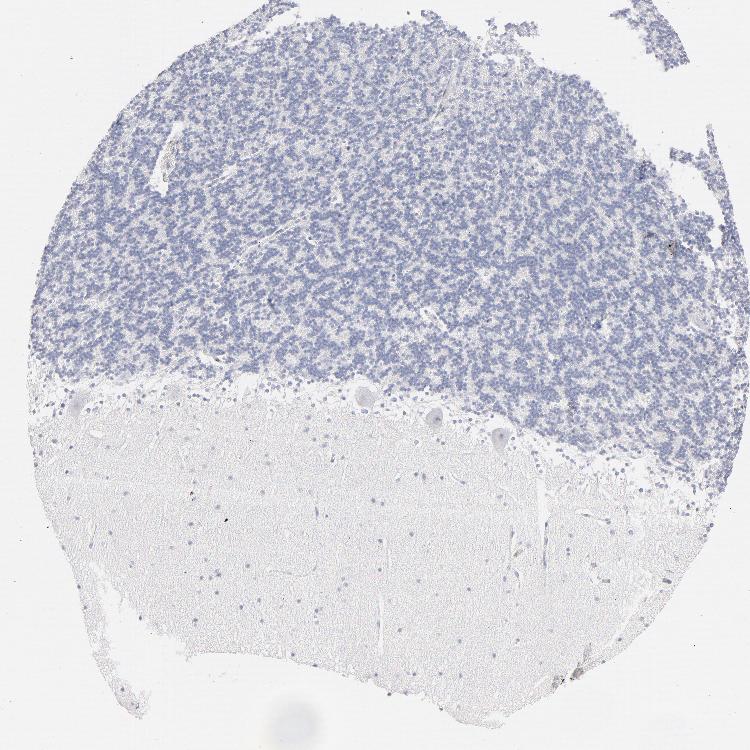

BRAIN CEREBELLUM Show tissue menu

CEREBELLUM - Expression summary

CEREBELLUM - Antibody stainingi

Antibody staining in the annotated cell types in the current human tissue is reported as not detected, low, medium, or high, based on conventional immunohistochemistry profiling in selected tissues. This score is based on the combination of the staining intensity and fraction of stained cells.

Each image is clickable and will lead to virtual microscopy that enables deeper exploration of all samples and also displays staining intensity scores, fraction scores and subcellular localization as well as patient and tissue information for each sample.

Antibody HPA003898Antibody CAB002163Antibody CAB016312

Purkinje cells Not detectedNot detectedNot detected

Cells in granular layer Not detectedNot detectedNot detected

Cells in molecular layer Not detectedNot detectedNot detected